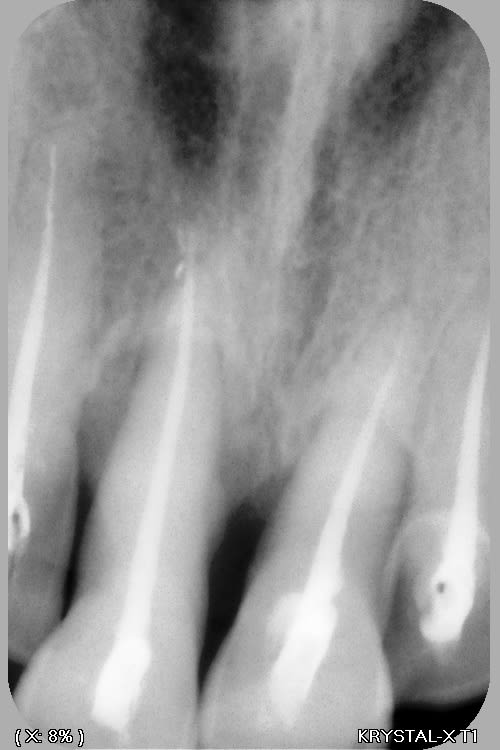

la suite

--